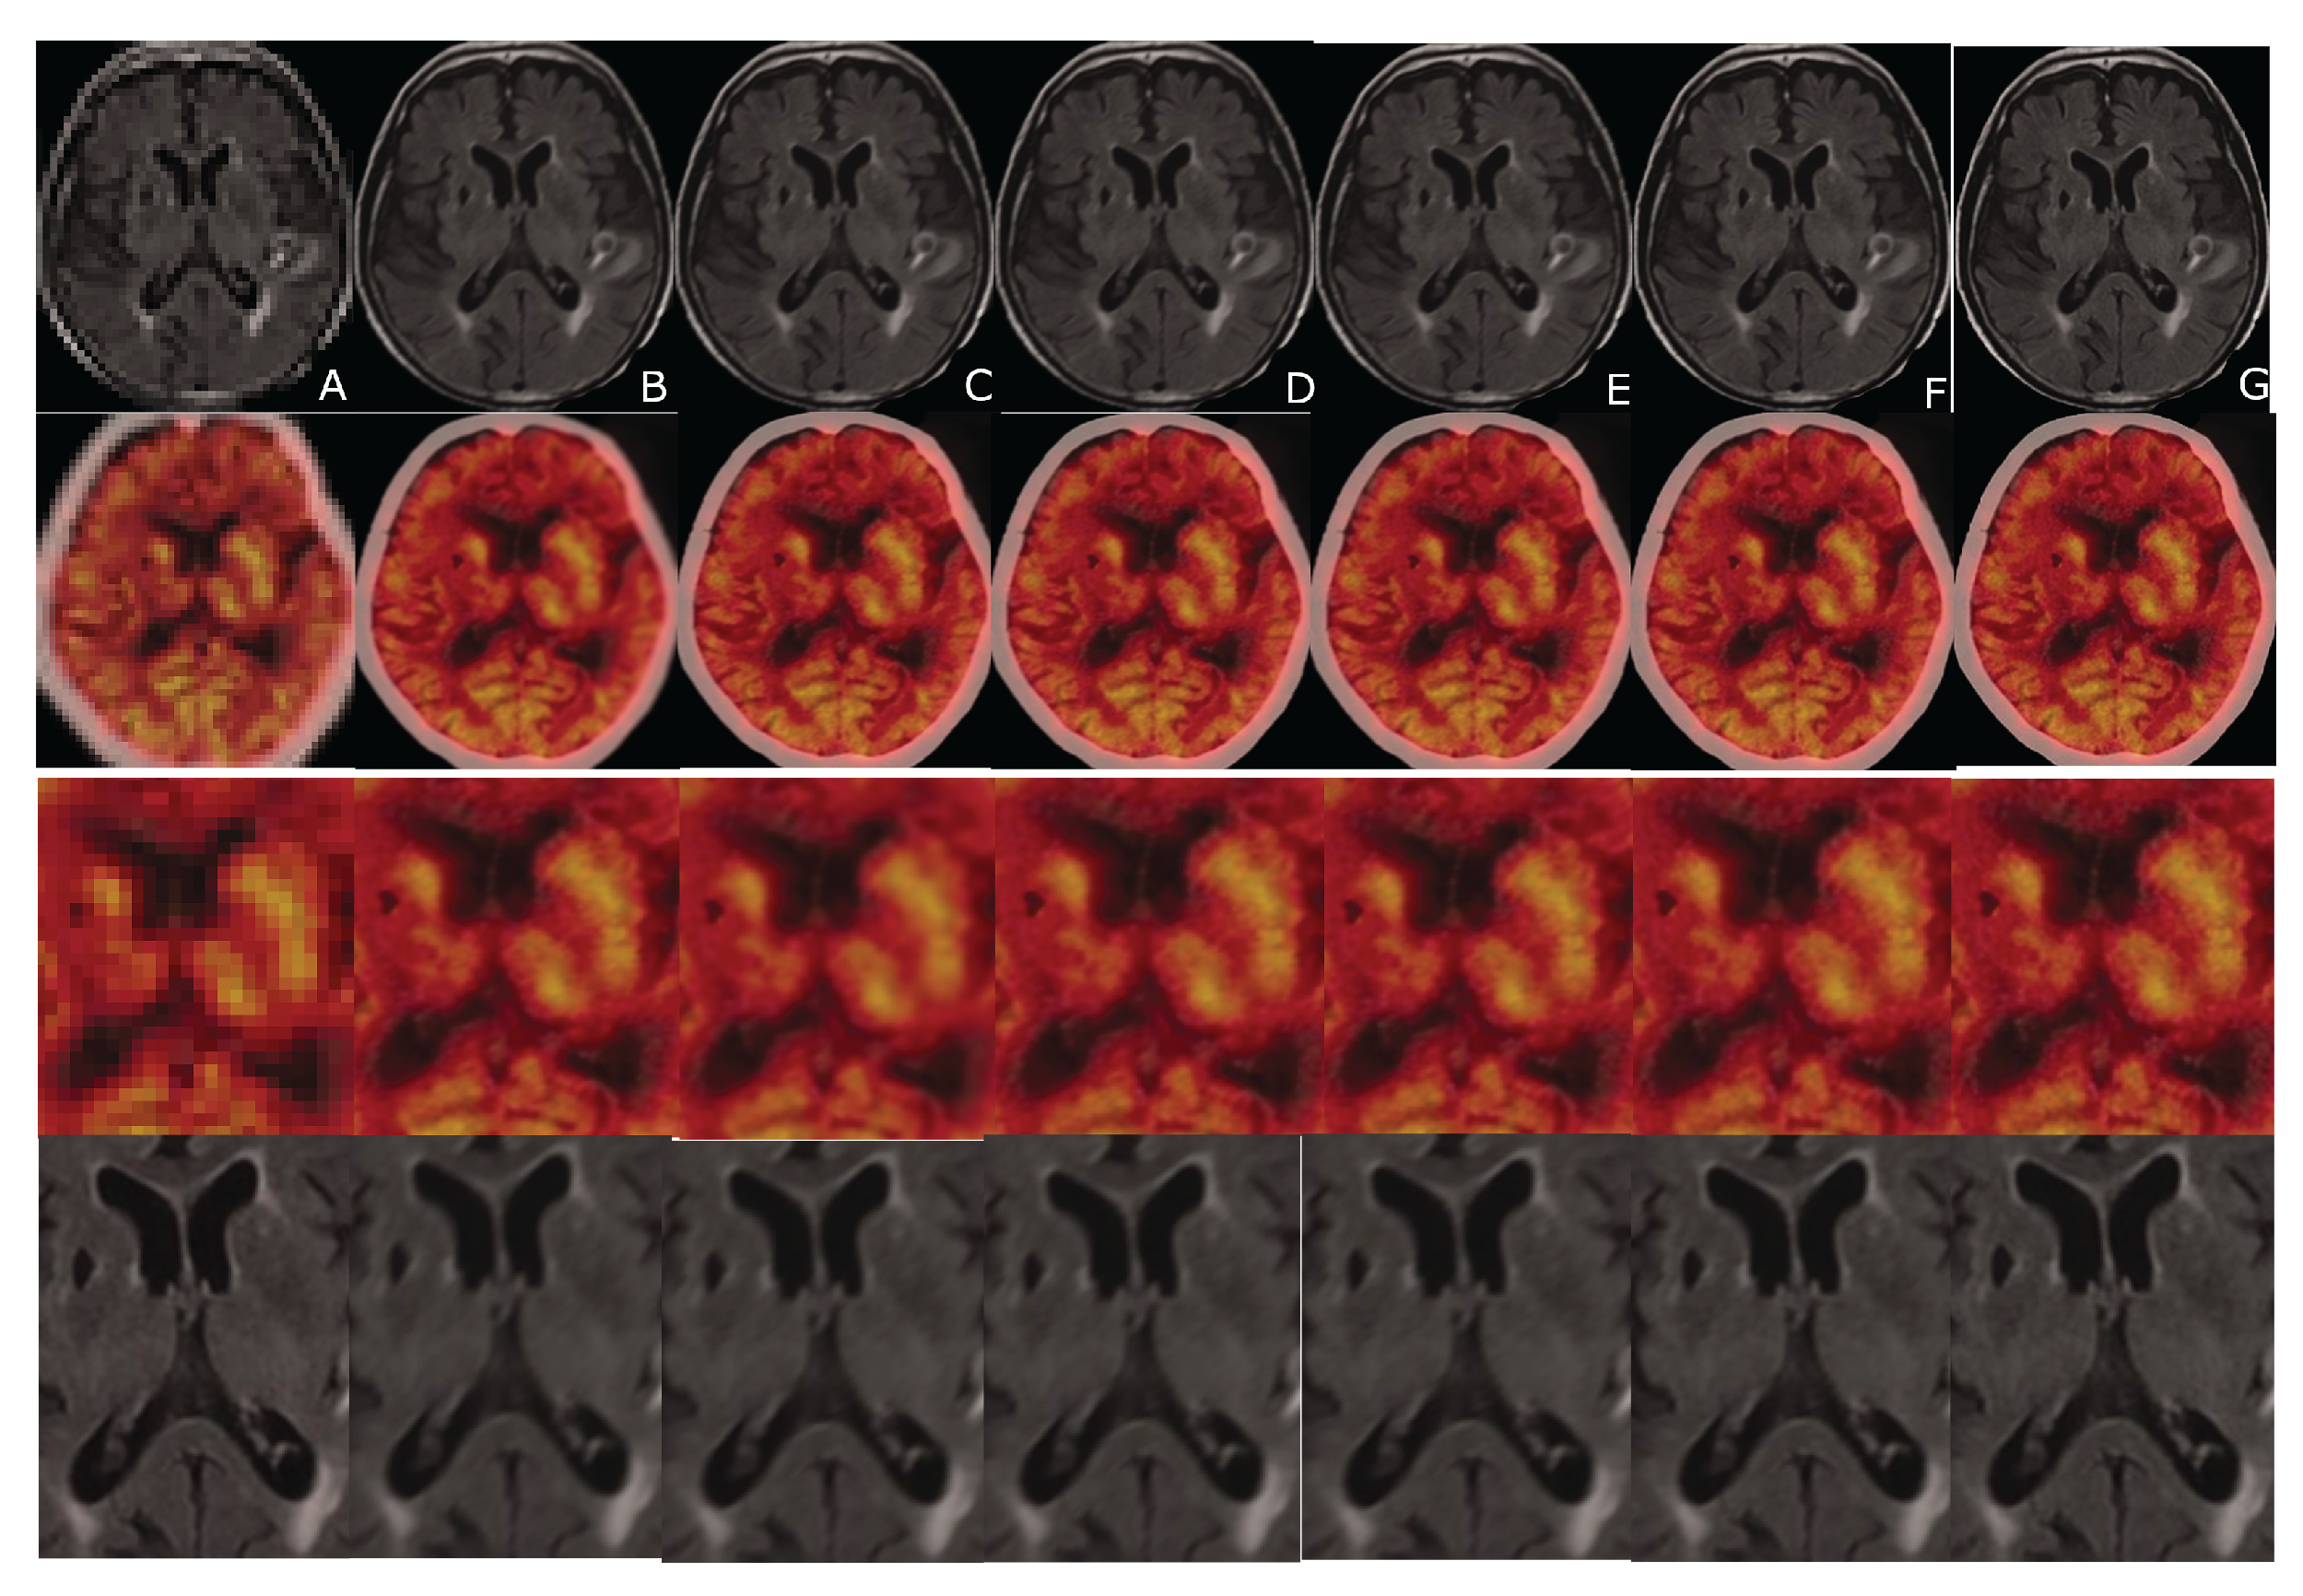

Figure 9.

An example of CT and FDG-PET data sets. From left to right: (A) LR input; (B) B-spline Cubic interpolation; (C) Non-Rigid Multi-Modal 3D Medical Image Registration Based on Foveated Modality Independent Neighbourhood Descriptor [25]; (D) Enhanced deep residual networks for single Image Super-Resolution [13]; (E) Image super-resolution using very deep residual channel attention networks [14]; (F) Residual dense network for Image Super-Resolution [15]; (G) the presented algorithm. The 3rd and the 4th row: the cropped and zoomed scans.